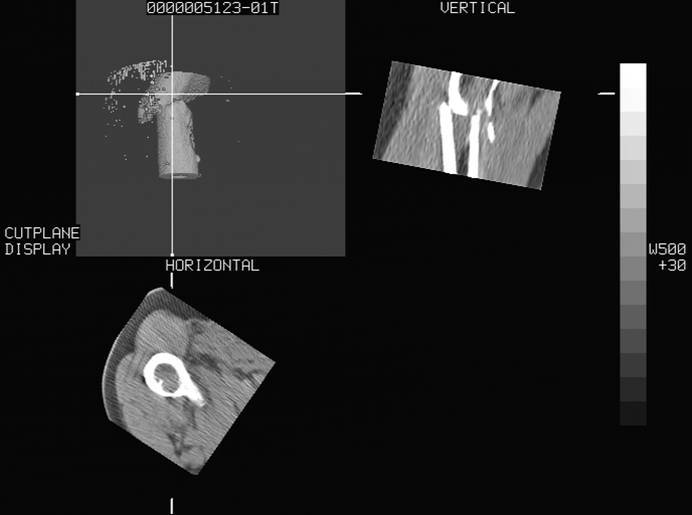

标题: CT16696:M53Y,左股骨上段骨折。 [打印本页]

标题: CT16696:M53Y,左股骨上段骨折。

图像不太清楚,左股骨上段外伤性骨折?病理性骨折?

左股骨上段粉碎性骨折

左股骨上段粉碎性骨折,不排除病理性骨折可能。

考虑骨肉瘤伴病理骨折

考虑:骨肉瘤伴病理骨折.

病理性骨折,考虑转移所致.